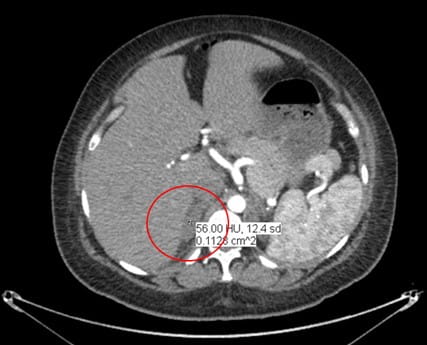

A CT angiogram (CTa) ruled out a pulmonary embolus (PE), but revealed an interval development of a 5.3 x 3 cm left adrenal hemorrhage (see Image 2).

Image 2: CT angiogram remarkable for interval development of a 5.3 x 3 cm left adrenal mass with subtle infiltration of adjacent fat, consistent with left adrenal hemorrhage.